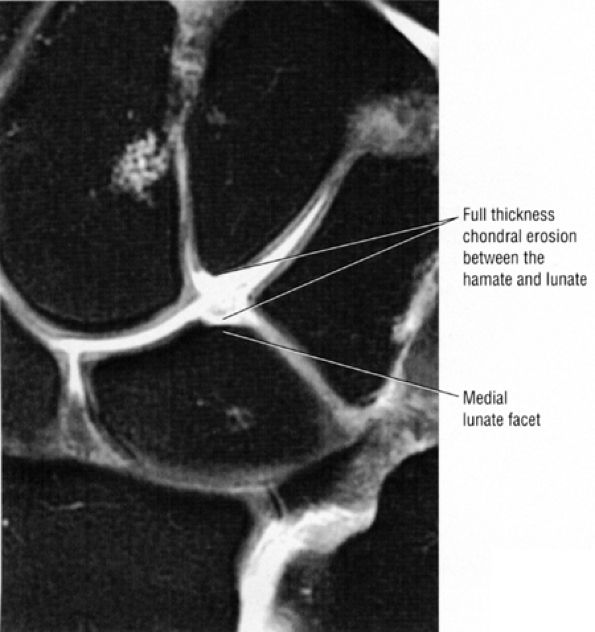

FIGURE 10.31 ● Normal coronal anatomy. (A) Fatty atrophy or denervation of the thenar muscles raises the possibility of median neuritis, and in such cases the median nerve is closely examined for enlargement or increased signal. (B) Tenosynovitis of the flexor tendons with fluid in the tendon sheaths can occasionally cause enough mass effect on the median nerve to cause median neuritis. (C) The first carpometacarpal joint (the articulation between the trapezium and the base of the first metacarpal) is a common location for degenerative arthrosis, often visualized at the corner of a coronal image. (D) Fluid in the pisotriquetral recess is a common finding. In the absence of other findings such as degenerative changes at the joint, a small amount of fluid in the pisotriquetral recess is probably of no significance. (E) Fractures of the distal scaphoid extending to the articular surface should be characterized as entering the lunate fossa (the radial articulation with the lunate) or the scaphoid fossa (the radial articulation with the scaphoid). Such articular extension, particularly if depressed or displaced, can lead to significant radiocarpal degenerative disease. (F) The triscaphe joint consists of the distal pole of the scaphoid articulating with the trapezoid and trapezium and is considered the second most common site of wrist arthrosis. (G) The proximal row should normally form a continuous smooth convex curve. Any subtle offset of the triquetrum from the lunate, or the scaphoid from the lunate, is suggestive of a tear of the lunotriquetral or scapholunate ligaments. (H) The triangular fibrocartilage attachment to the radius may attach to hyaline articular cartilage, and it is important not to mistake the gray cartilage signal at the attachment for a tear, which is usually of fluid signal intensity. (I) The proximal pole of the hamate may occasionally articulate with a normal variant type II lunate facet located on the distal ulnar aspect of the lunate. When this occurs, degenerative changes are visualized at the hamate-lunate articulation in almost half of cases. (J) Small degenerative perforations in the membranous component of the scapholunate ligament are not uncommon in older patients, and in this population they may be asymptomatic and unassociated with carpal instability. (K) The TFC has insertions at the tip and at the base of the ulnar styloid. Therefore, fractures at the base of the ulnar styloid may disrupt the integrity of the TFC and potentially cause distal radial ulnar joint instability. (L) On coronal images through the dorsal wrist, the dorsal component of the scapholunate ligament may occasionally be discretely identified. The dorsal component is considered the most important of the scapholunate ligament components for maintaining carpal stability. (M) Another significant and commonly overlooked location for degenerative arthrosis is at the base of the third metacarpal, where a common protuberance, called a carpal boss, articulates with the capitate. Unusually prominent carpal bosses may become hypertrophic and articulate with a spur on the distal capitate, which can often be palpated by the patient as a tender bump just beneath the skin along the dorsal wrist. (N) Ganglion cysts can be visualized extending through the dorsal capsular ligaments on coronal images through the dorsal wrist. Common sites of origin are the scapholunate ligament, the triscaphe joint, and the third carpometacarpal joint (often associated with degenerative change at a carpal boss).